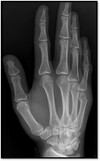

54

What pathology is shown here?

Boxers #